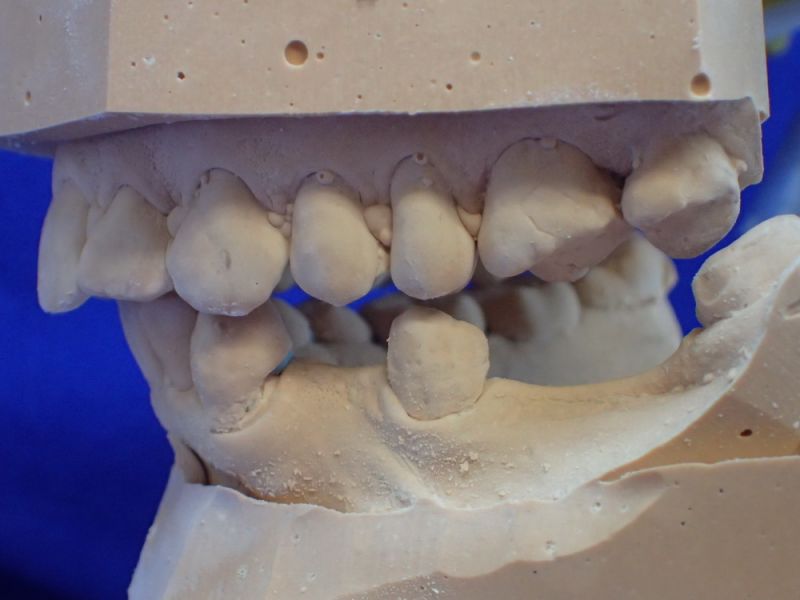

Erkennbar ist die massive Abweichung der habituellen Bisslage von der neuromuskulär zentrierten Bisslage.